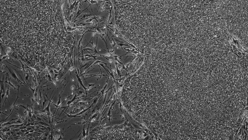

El uso de células madre pluripotentes (iPS) constituye la opción más prometedora en el campo de la medicina regenerativa. No en vano, estas iPS tienen la capacidad de convertirse en cualquier célula de cualquier tejido del organismo, por lo que pueden cultivarse en una placa de laboratorio y, una vez diferenciadas en el tipo de célula deseada, trasplantarse en el paciente, dividirse y regenerar el órgano o tejido dañado. Sin embargo, y si bien ya se ha logrado que estas iPS se conviertan en células del miocardio y en neuronas, no se había conseguido que se transformen en células madre hematopoyéticas, esto es, en células madre capaces de convertirse en cualquier célula sanguínea, caso de un glóbulo rojo, un glóbulo blanco o una plaqueta. O así ha sido hasta ahora, dado que investigadores del Hospital Infantil de Boston y de la Universidad Weill Cornell Medicine , (EE.UU.) han logrado, por primera vez, obtener células madre hematopoyéticas a partir de iPS , lo que abre la puerta a una nueva vía de tratamiento de las enfermedades de la sangre.

En el nuevo estudio, los autores utilizaron tanto células madre embrionarias como iPS y las expusieron a señales químicas para inducir su diferenciación en células y tejidos específicos del desarrollo embrionario . Concretamente, lo que obtuvieron fue un tejido embrionario denominado ‘endotelio hemogénico’ del que derivan las células madre hematopoyéticas –si bien hasta ahora nunca se ha logrado llevar a cabo la transformación en un laboratorio.